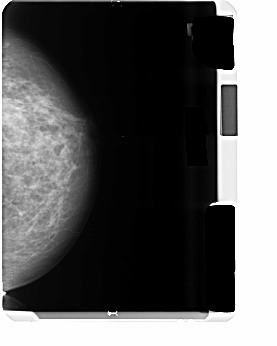

B_3500_1.LEFT_CC

LEFT_CC LINES 5182 PIXELS_PER_LINE 4146 BITS_PER_PIXEL 12 RESOLUTION 50 NON_OVERLAY